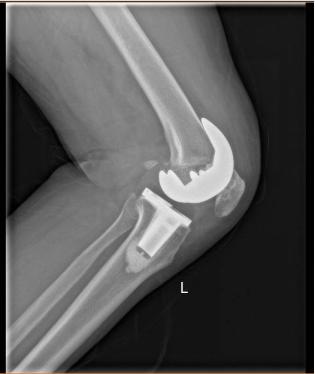

反复讨论制定了完善的膝关节置换手术计划和术后康复方案,刘宁主任向范阿姨介绍道:膝关节置换术就是将膝关节损坏的部分切除,换上新的活动关节,使膝关节稳固,受力平衡,从而消除疼痛,手术使用的材料是钛合金部件和高分子量聚乙烯垫片,跟人体相容性好,极少出现排斥反应。

术后第1天,范阿姨便能下地无痛行走,这让她感到十分惊讶和欣喜!术后第5天,范阿姨便顺利出院。